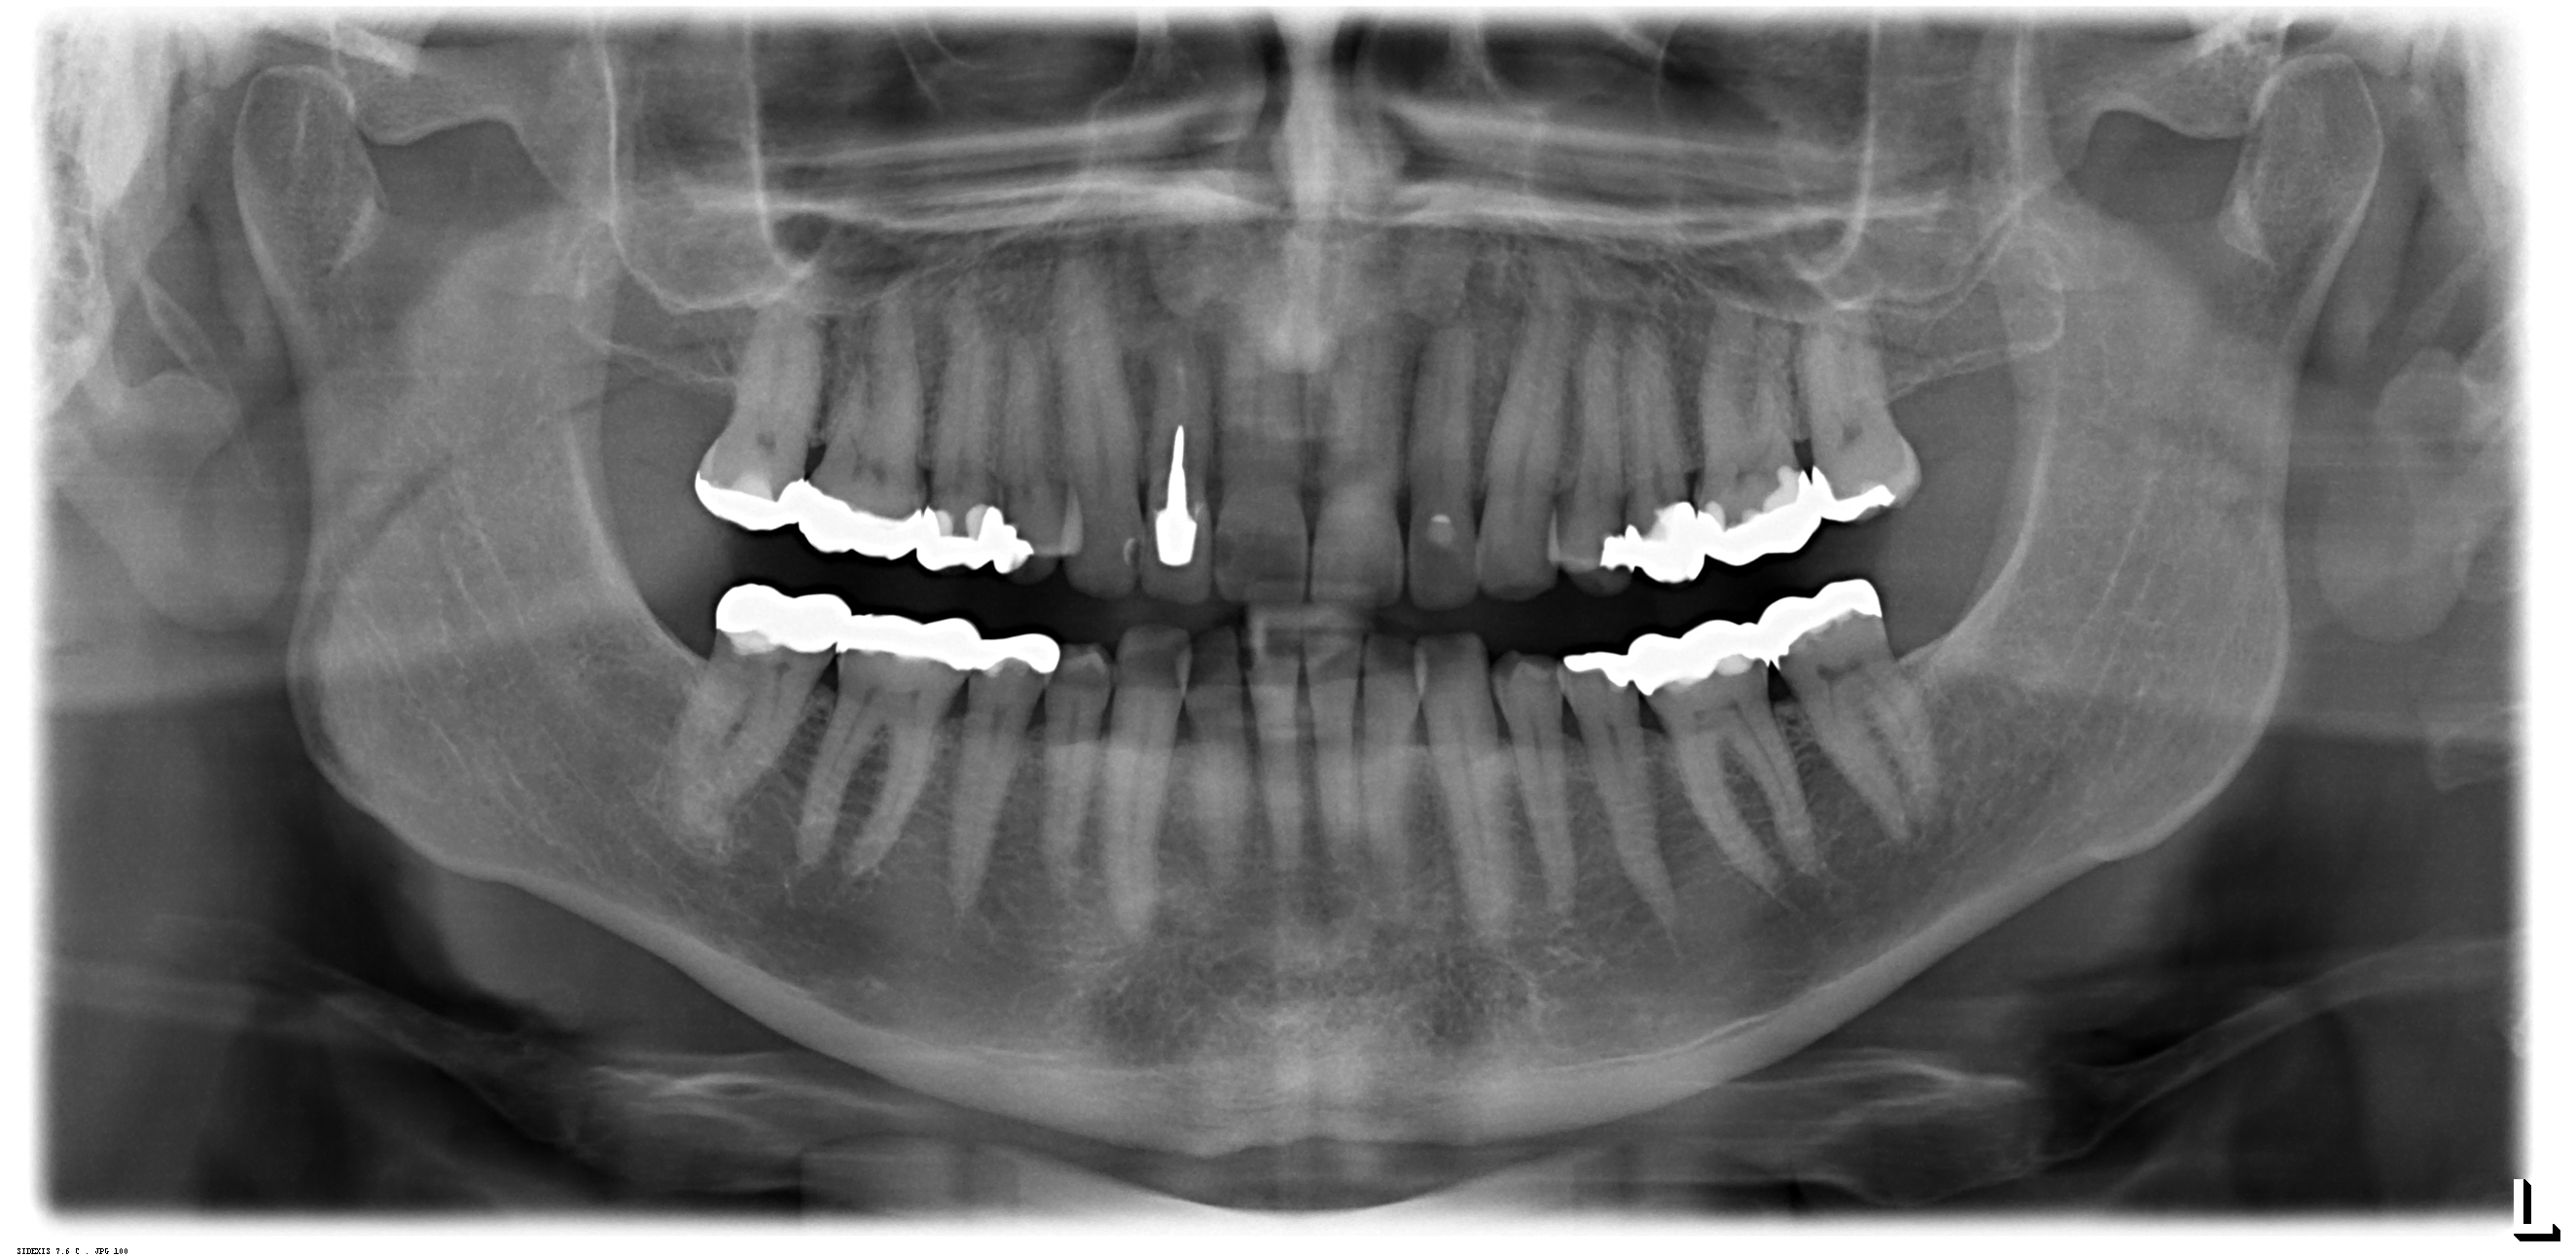

Digitales Röntgen

Röntgenaufnahmen als Einzelaufnahmen wie auch Übersichtsaufnahmen des ganzen Kiefers werden in unserer Praxis digital erstellt.

Die Strahlenbelastung gegenüber herkömmlichen Röntgenaufnahmen ist deutlich reduziert. Die Diagnostik verbessert.

Da keine Entwickler und Fixierbäder benötigt werden ist die Umwelt entlastet.